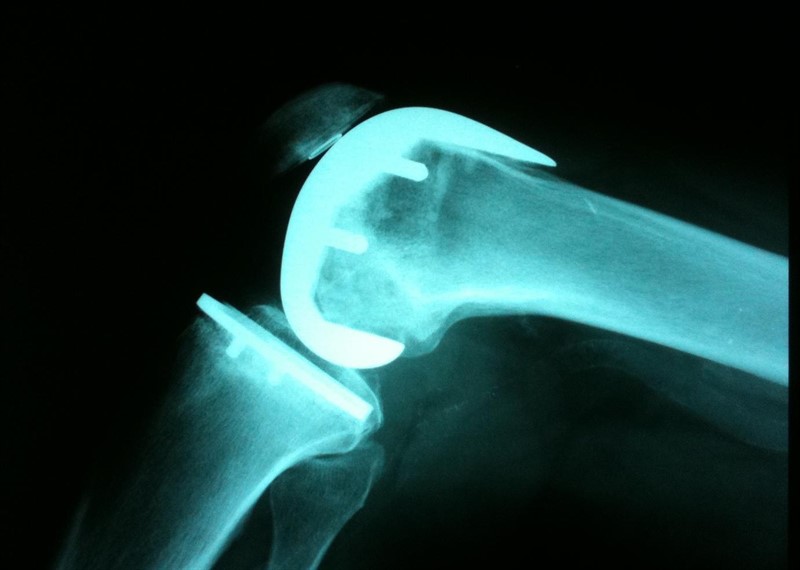

Resultados relevantes para el paciente de reemplazo de rodilla unicompartimental versus total

27 febrero 2019

BMJ, 21 de febrero de 2019 El reemplazo de rodilla unicompartimental (RRU) o el reemplazo total de rodilla (RTR) son opciones viables para el tratamiento de la osteoartritis unicompartimental aislada. Al comparar directamente los dos tratamientos, el estudio demuestra mejores resultados para RRU en varios dominios de resultados. Sin embargo, el riesgo de cirugía de revisión fue menor para la RTR. Esta información debe estar disponible para los pacientes como parte del proceso compartido de toma de decisiones al elegir las opciones de tratamiento.